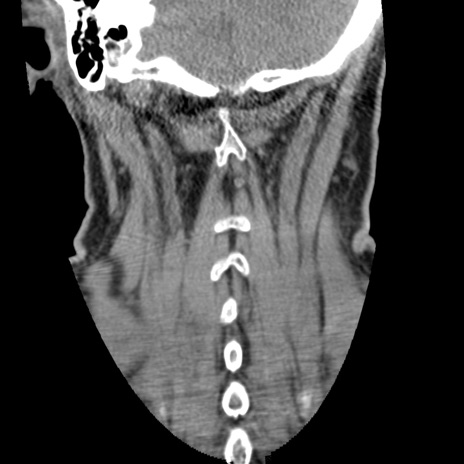

症例50 頚椎CT(冠状断像)

頚椎CT